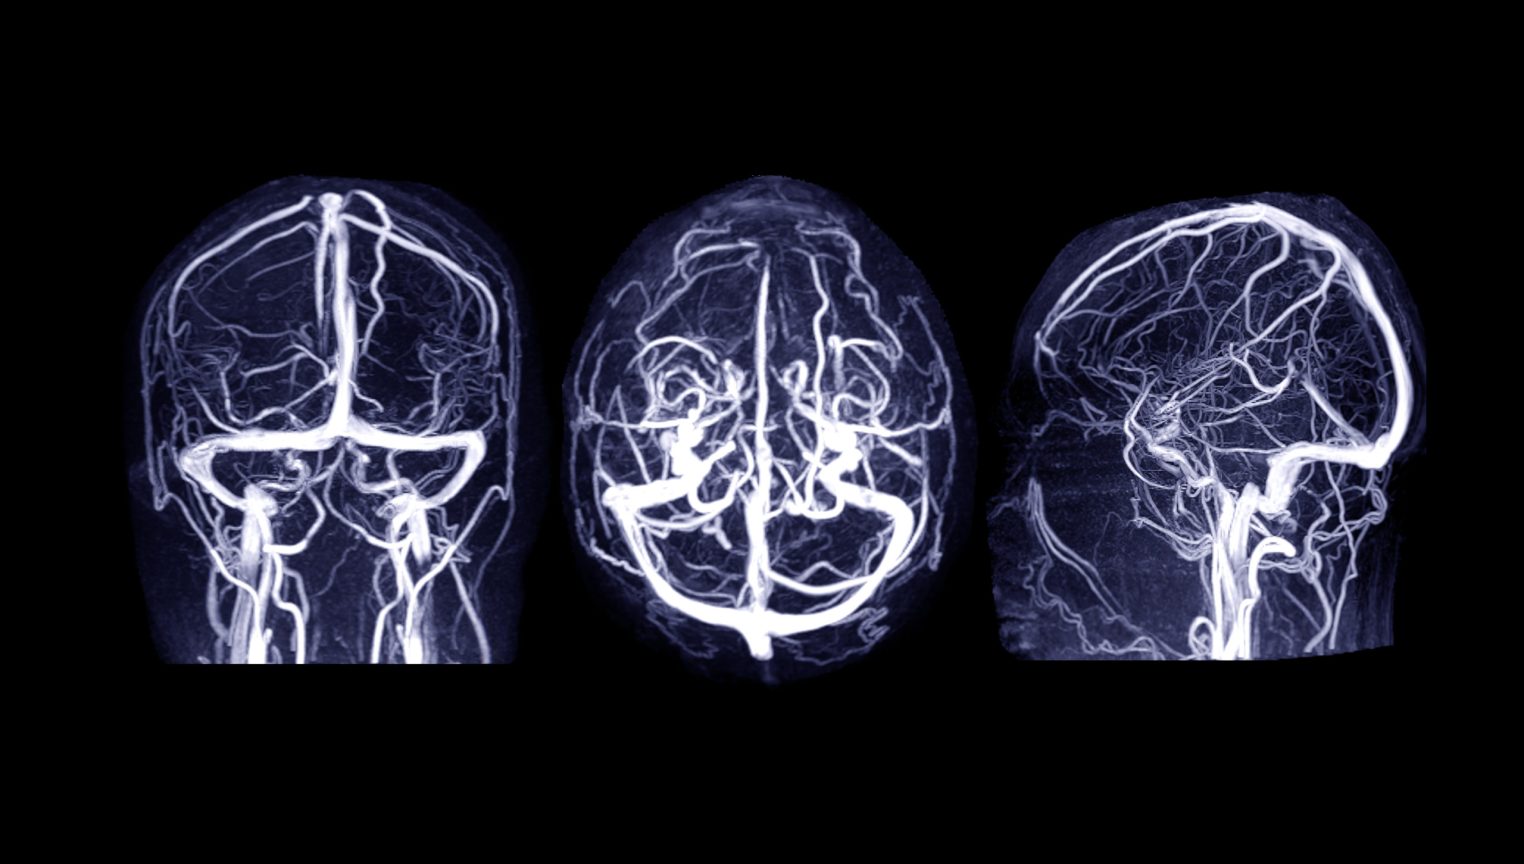

Diagnosticul de tromboza venoasa cerebrala este stabilit de catre medicul neurolog in baza istoricului medical al pacientului si a examenului obiectiv. Este obligatorie examinarea imagistica cerebrala (CT sau IRM) cu substanta de contrast.